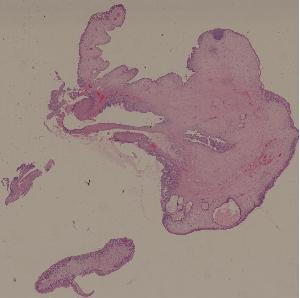

23.炎性息肉

低倍视野